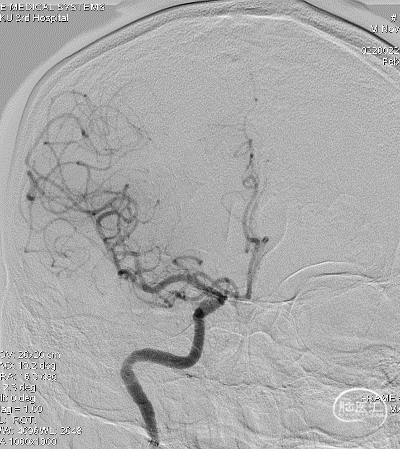

局麻,右股动脉入路置8F短鞘,导管导丝技术将8F MPA置于右C1末端,造影确认右M1急性闭塞,侧支代偿差。

以Transend-14导丝 + Headway21导管到达M1中段,Sofia Plus顺畅到位(M1中段),ADATP技术抽吸取栓,一次成功取通,前向血流TICI 3级,无栓子逃逸及原位狭窄,穿刺至开通时间仅用时9min。

DSA造影见右侧大脑中动脉M1中段以远闭塞,ACA向MCA区域仅少量代偿。Sofia Plus在Headway21导管及Transend导丝引导下,很顺畅通过虹吸段等部位,到达M1中段。

采用ADAPT技术,血流快速复通;最右图为Sofia Plus导管前端及取出血栓。